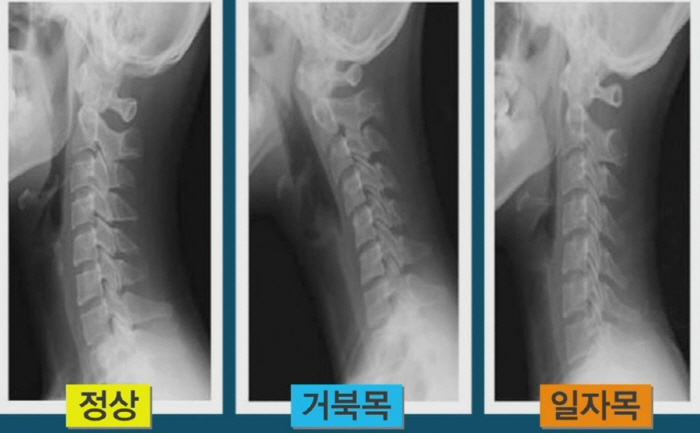

목 디스크 증상 총 정리 중 원인이고요. 한방 의학정보에 의하면 목 디스크는 목 뼈 사이 추간판이 파열됐거나 탈출되어 경추 신경의 자극, 압박으로 인하여 목, 어깨, 등, 팔 등 통증과 신경학적 증상이 있는 질환이예요.

경추는 제일 위쪽 목에 있는 7개의 뼈이라고 합니다. 경추는 운동성이 크므로 경추의 추간판은 압력에 의해 탈출되어 척수, 신경근을 억압되게 된다 하였습니다.

건강한 목은 c커브이예요. 하지만 컴퓨터, 스마트폰, 꼬이게된 생활습관으로 인하여 일자목이 됐을 경우, 목 뼈가 펴지며 혈관을 누르게 되기도 합니다. 이로 인하여 혈액 순환에 문제가 생기고 산소 공급이 잘 되지 않아 두통, 어지럼증, 현기증, 이명 등이 사료됩니다. 그리고 목을 눌렀을 때 두통과 현기증이 일어날 수도 있어요.